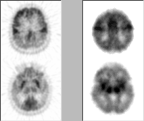

Case 4

Click on one or more of the images above to view full-size image(s).

- Female patient (born 1910); scan on left from 1984

- Female normal control (born 1917); scan on right